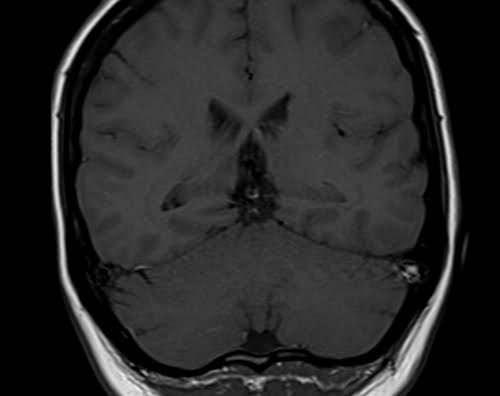

Brain epilipsy protocol mri coronal T1 images